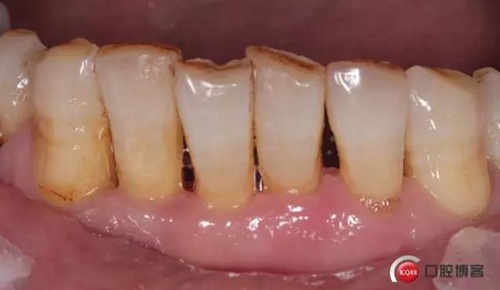

檢查:口腔衛(wèi)生狀況欠佳,牙面可見大量色素附著,牙石II°,尤以下頜前牙舌側(cè)及后牙頰側(cè)為重。牙齦紅腫,BI3-4°,PD下頜前牙區(qū)4-6mm。31松動III°,溫度測試無反應,叩不適。32、41、42松II°+,32溫度測試遲鈍,叩(-)。

檢查:口腔衛(wèi)生狀況一般,下頜前牙區(qū)牙齦色澤尚可,牙齦位置退縮,松動度減輕。